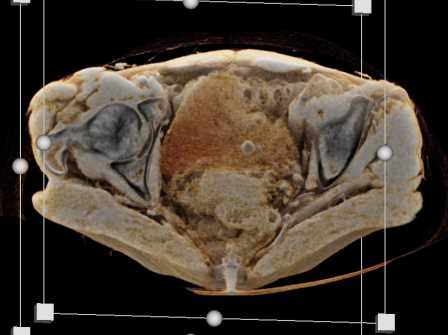

Urachal Carcinoma of the Bladder